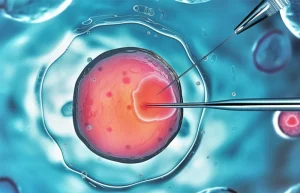

Sinh thiết phôi là kỹ thuật lấy một hoặc một vài tế bào của phôi để phân tích di truyền trước khi chuyển phôi vào tử cung. Mục tiêu chính là phát hiện các bất thường nhiễm sắc thể hoặc bệnh di truyền có thể ảnh hưởng đến khả năng làm tổ, phát triển thai hoặc sức khỏe em bé sau sinh.

Trong thực hành lâm sàng hiện đại, sinh thiết phôi chủ yếu được thực hiện ở giai đoạn phôi nang ngày 5 – 6, khi phôi đã phát triển thành cấu trúc ổn định hơn.

2. Sinh thiết phôi ngày 5–6 (phôi nang)

Đây là phương pháp được ưu tiên hiện nay. Ở giai đoạn này, phôi đã phân hóa thành:

- Khối tế bào trong (ICM): phát triển thành thai nhi

- Lớp tế bào lá nuôi (TE): phát triển thành nhau thai

Sinh thiết sẽ lấy 5–10 tế bào từ lớp TE, không xâm lấn vào khối tế bào trong. Do đó, về mặt sinh học: